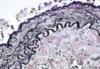

The name of the coloration which was used:

Massons trichrome and Mallorys trichrome.